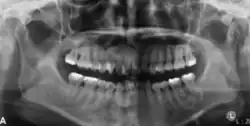

Panoramic radiograph showing a radiolucency around the distal root of the first mandibular molar[25]

In its early stages, central ossifying fibroma (COF) appears as a small, well-defined radiolucent lesion due to its fibrous tissue content. Differential diagnoses at this stage include periapical pathology, central giant cell granuloma, and ameloblastoma.[22][23] As the lesion matures, it exhibits a mixed radiolucent-radiopaque appearance due to progressive calcification.[22] At this stage, it should be differentiated from other mixed jaw lesions such as fibrous dysplasia, calcifying epithelial odontogenic tumour, adenomatoid odontogenic tumour, and condensing osteitis.[22] In its mature form, COF may appear predominantly radiopaque, resembling lesions like odontomas, osteoblastomas, or osteosarcomas radiographically.

COF typically presents with well-defined, smooth, and often corticated borders. As a central lesion, it originates within the medullary bone and expands concentrically in all directions.[24] With growth, it may cause tooth displacement, root resorption, inferior displacement of the mandibular canal, and loss or alteration of the lamina dura of adjacent teeth.[25]